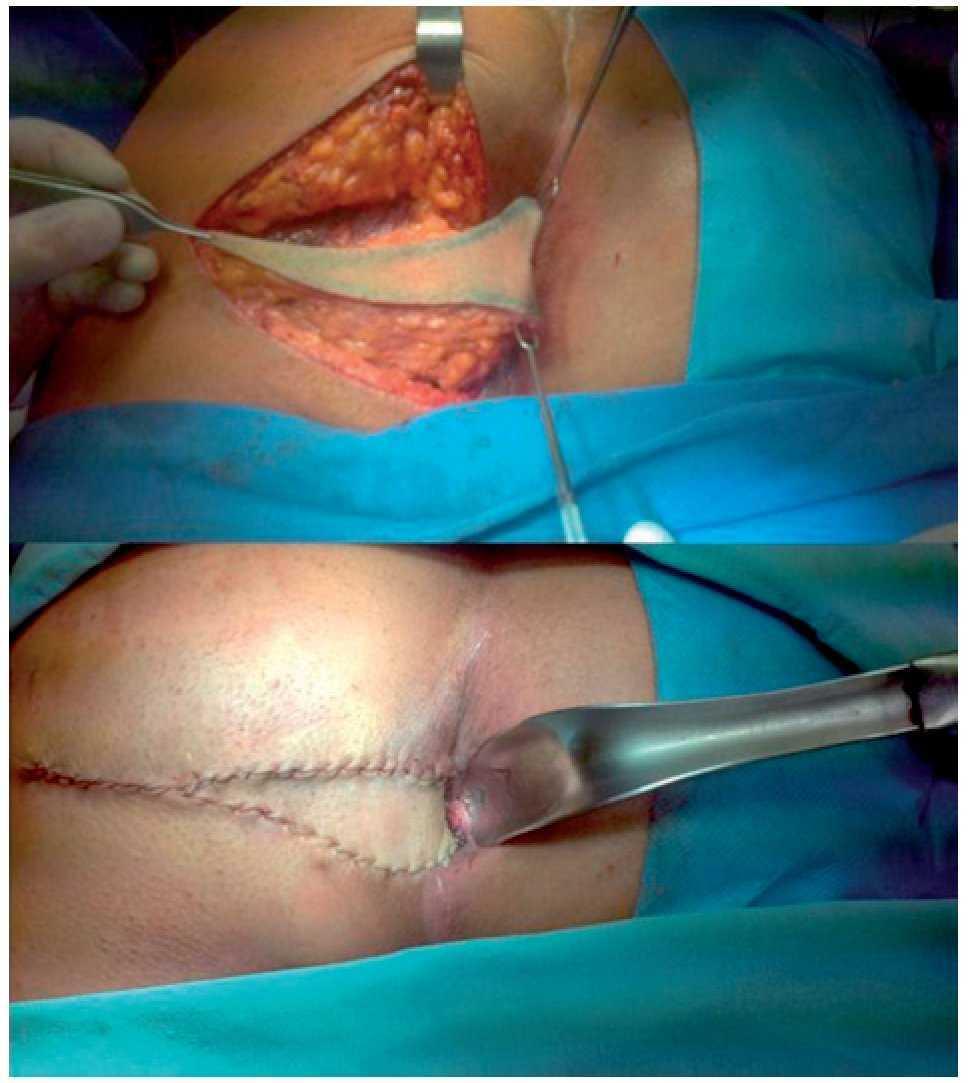

The patient is a 58-year-old man with a perianal lesion of 1-year progression that reached 3 cm in diameter causing pruritus and intermittent bleeding. He had received topical treatment with no response and therefore underwent an incisional biopsy; the histopathologic report was basal cell carcinoma and so he was referred to us for his integral evaluation and management. Deep structure involvement was not apparent in the endoanal ultrasound. Physical examination did not reveal inguinal adenopathies or other dermal lesions. Paraclinical studies classified the disease as T2N0M0, with no treatment contraindications. The patient had no prior history of radiotherapy or previous trauma. Local wide resection was performed with an intraoperative margin evaluation and the defect was closed with a V¿Y flap. Follow-up is currently at 13 months and there has been no disease recurrence (Figs. 1-3).

Figure 2. Local resection with 1 cm margin and V-Y flap to cover the resultant defect.